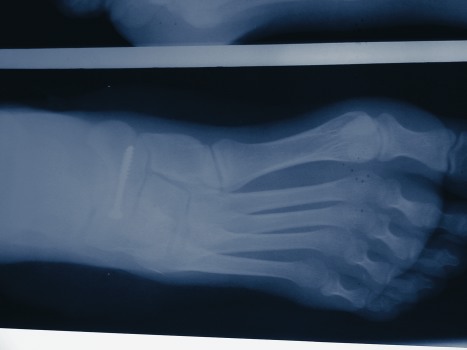

Stress fractures are one of the more common lower extremity injuries in runners. The most common sites include the metatarsals and the tibia. The best indicator that a stress fracture may have occurred is increasing pain as the workout progresses. A focal spot of pain, pain with loading, pain with percussion over the area and localized edema are excellent clinical indicators of a possible fracture. One diagnostic test that works well is having the patient hop on the injured side. This produces sharp, pinpoint pain. One may also use the hop test to determine if the bone is healed enough for the patient to return to activity. In the early stages, radiographic findings are usually insignificant so one must follow negative X-rays with further testing. The triple phase bone scan (TPBS) remains the most sensitive indicator of a stress fracture. Many physicians favor MRI but there are more false positives with a MRI than the TPBS. When patients have stress fractures of the tarsal bones, particularly the navicular, one should obtain a CT scan in the coronal and axial plane with 1.5 mm cuts in order to ascertain the extent of the fracture and help guide treatment. While stress fractures often occur after over-training, multiple stress fractures in an experienced runner require much further investigation. Females require special attention due to the possibility of the female athlete triad of amenorrhea, anorexia and osteoporosis. If one suspects this triad, the clinician should refer the patient for nutritional and psychological consultation. Keep in mind that there will be a significantly high rate of denial in an athlete with this syndrome. Pay special attention to the biomechanical examination when patients present with recurrent injuries and inquire about changes in training including possible increases in mileage or the intensity of the workouts. In the colder climates, indoor track and, in the high school population, running in the school hallways, are big contributors to running injuries and increased stress fractures.14,15

Conservative treatment of most stress fractures includes no running and only non-weightbearing cross training. Several stress fractures require casting and/or non-weightbearing including the base of the fifth metatarsal, femur, navicular and cuboid. Matheson’s 1987 analysis of 320 bone scans positive for stress fractures found the tarsal bones to be the second most common site, accounting for 25 percent of the positive bone scans.16 Navicular stress fractures in particular have been found to occur in runners at a surprisingly high rate. This bears mention as diagnosis and treatment of navicular stress fractures requires a high index of suspicion and eight to 10 weeks of immobilization including non-weightbearing. When conservative treatment fails to heal a navicular stress fracture, one should proceed to open reduction internal fixation (ORIF). Two articles show a faster return to activity following surgical management of navicular fractures than conservative treatment.17,18 Bone stimulation is an additional modality that may help get an injured athlete back faster from a stress fracture. There is very little published to support using a bone stimulator but a study by Saxena in Foot and Ankle Quarterly showed that using a pulsed electromagnetic field (PEMF) allowed athletes to return much quicker from their stress fractures.19 The paper presented a small, prospective, unblended analysis of 73 stress fractures that were confirmed via bone scan, MRI or CT scan. The PEMF group returned to activity in 8.8 weeks versus the non-PEMF group, which returned to activity in 17.6 weeks. Further scientific studies are warranted but even a few weeks of added training can mean a great difference to a professional runner or a college or high-school runner with a limited amount of eligibility to compete.